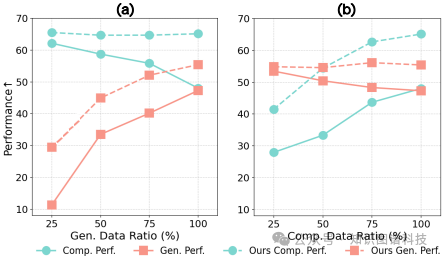

研究难点:该问题的研究难点包括:医疗数据的高规模和质量限制,以及理解和生成任务之间的冲突。具体来说,医疗数据的规模和多样性不足,且理解和生成任务需要不同的视觉细节处理方式,难以在同一模型中同时优化。

理解与生成任务之间的冲突

:理解任务通常剥离视觉细节以关注抽象,而生成任务需要详细保留,这使得在自回归多模态训练中保持前后LVLMs的一致性成为一个难题。尽管一些方法探索了理解与生成任务之间的相互增强,但性能提升仍然表现出递减的回报,性能退化仍是一个显著问题。